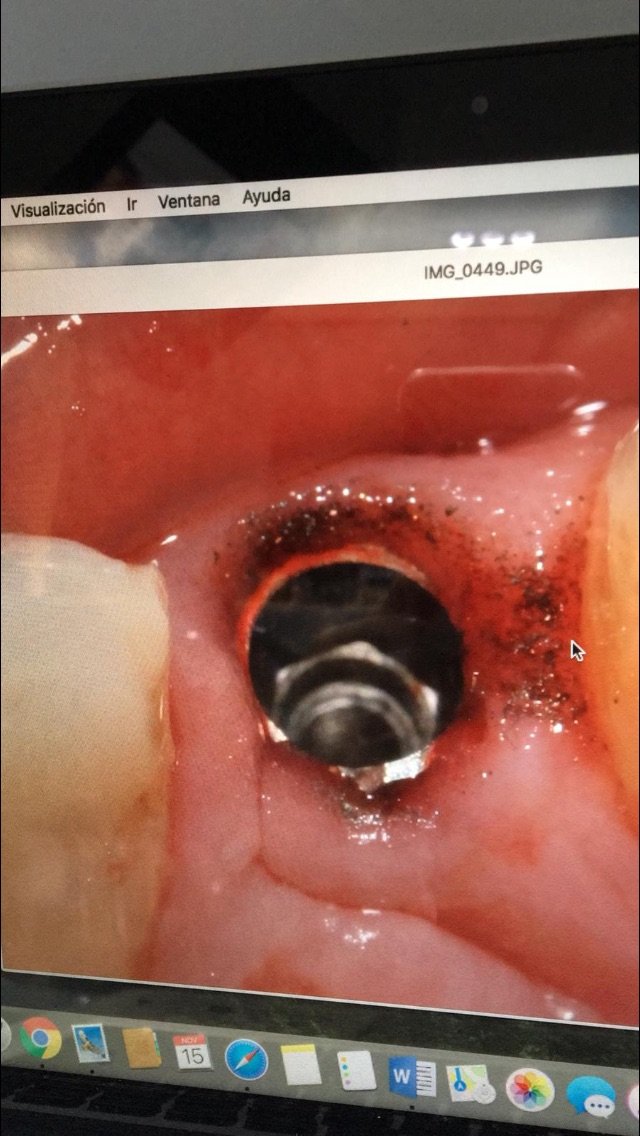

Ayuda para reconocer el Implante

Buenas noches, hace 2 meses le colocaron este implante con ese aditamento protesico para una protesis total removible, pero ese aditamento no ajusta bien y se desaloja del implante, pudieran [...]